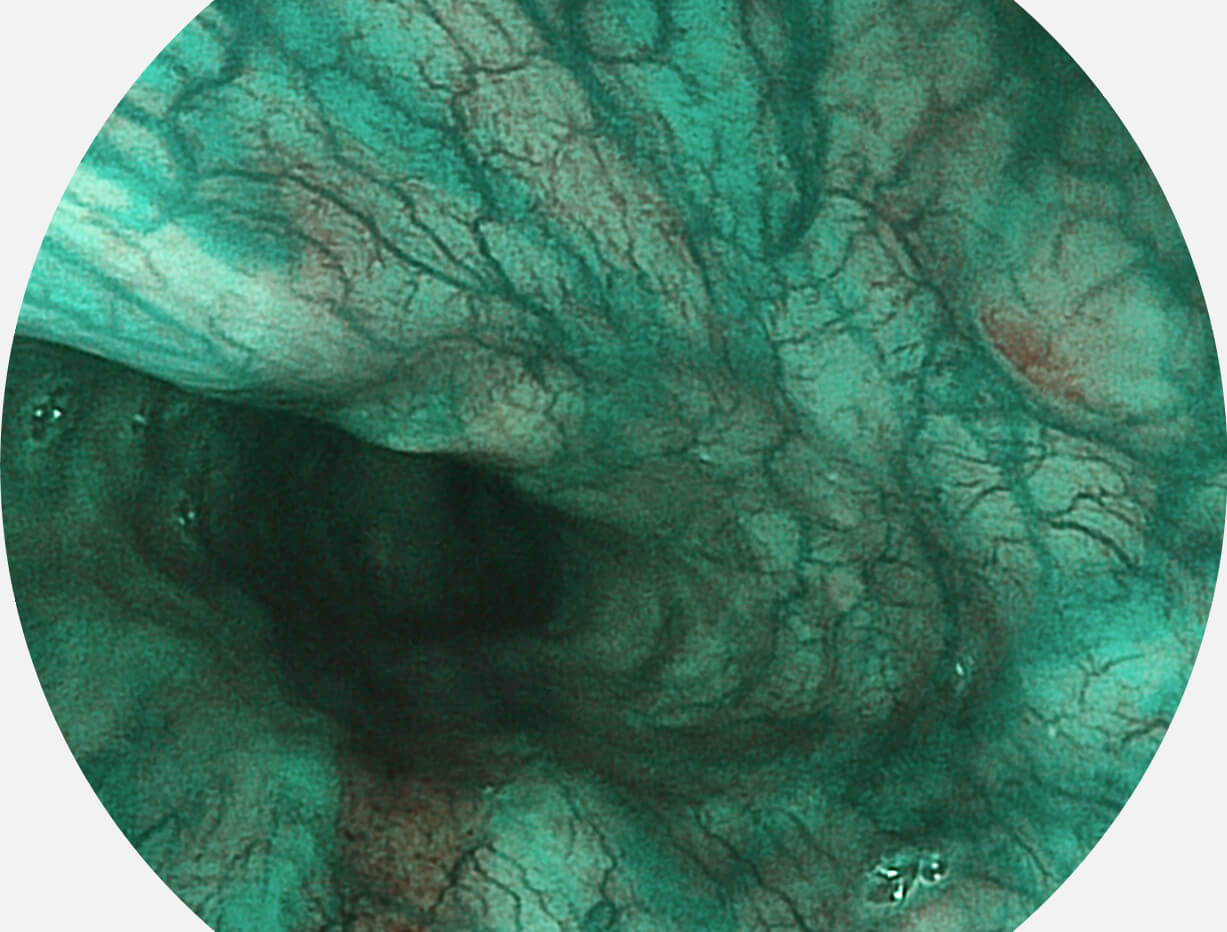

白光图像

SFI图像

Versatile Intelligent Staining Technology, VIST

强调浅层黏膜结构的同时,保证照明亮度和提升浅层微血管与中层血管颜色对比度,病变边界更清晰。